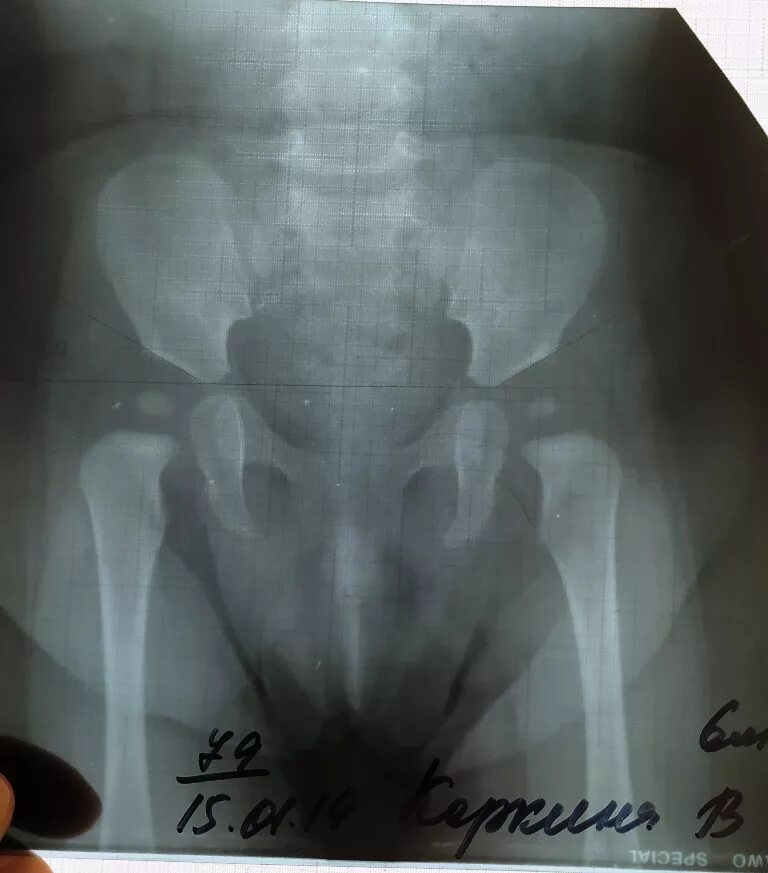

Дисплазия 7 лет